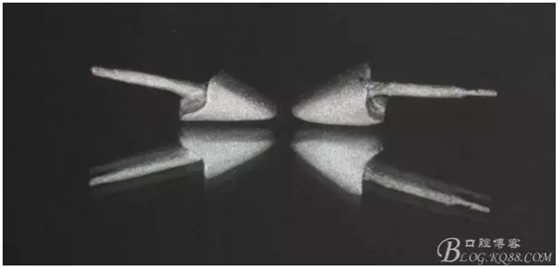

缺損太多 是必須用金屬樁修復(fù)的,

還要有足夠的牙本質(zhì)肩領(lǐng),大家現(xiàn)在可以看到患者的下頜套筒冠還是非常好的

雖然牙根折斷了,但是從這張片子可以看出我們的套筒冠還是很堅(jiān)挺的,有牙齦的退縮,但是牙槽骨致密程度非常好,值得欣慰